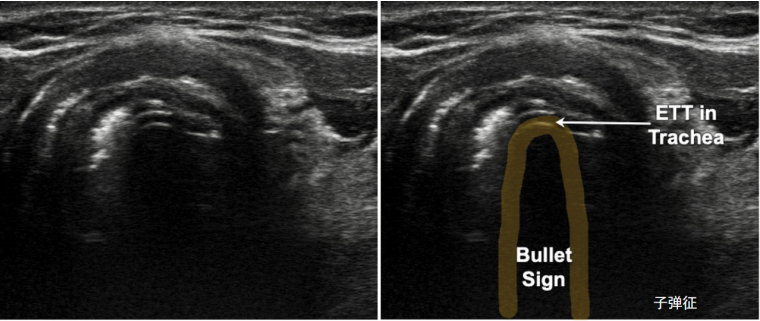

当气管插管进入气道后,在气道内壁可以看到一个典型的子弹头样的双轨征或子弹征,以此判断插管的位置。临床中在插管后扫查环状软骨切面,如果看到双轨征或子弹征(图17),即可确认气管插管在气道内。还可以将探头置于气道左侧, 食、颈动脉和气管围成的倒三角, 如果发现大的气道影和食影, 说明插管位置正确; 如果发现两个相同的气管影, 说明是双气管征(图18), 提示气管插管误入食

图17  子弹征

临床中我们可以通过一定的流程来判断插管的位置及深度,例如通过双气管征判断插管是否在气道内,通过肺滑动征是否对称来判断插管的深度。